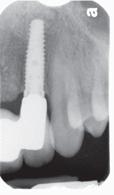

60 Top Dentists 2025

The annual Top Dentist list showcases excellence in dental care. See which New Hampshire dentists were voted by their peers as the most trustworthy.